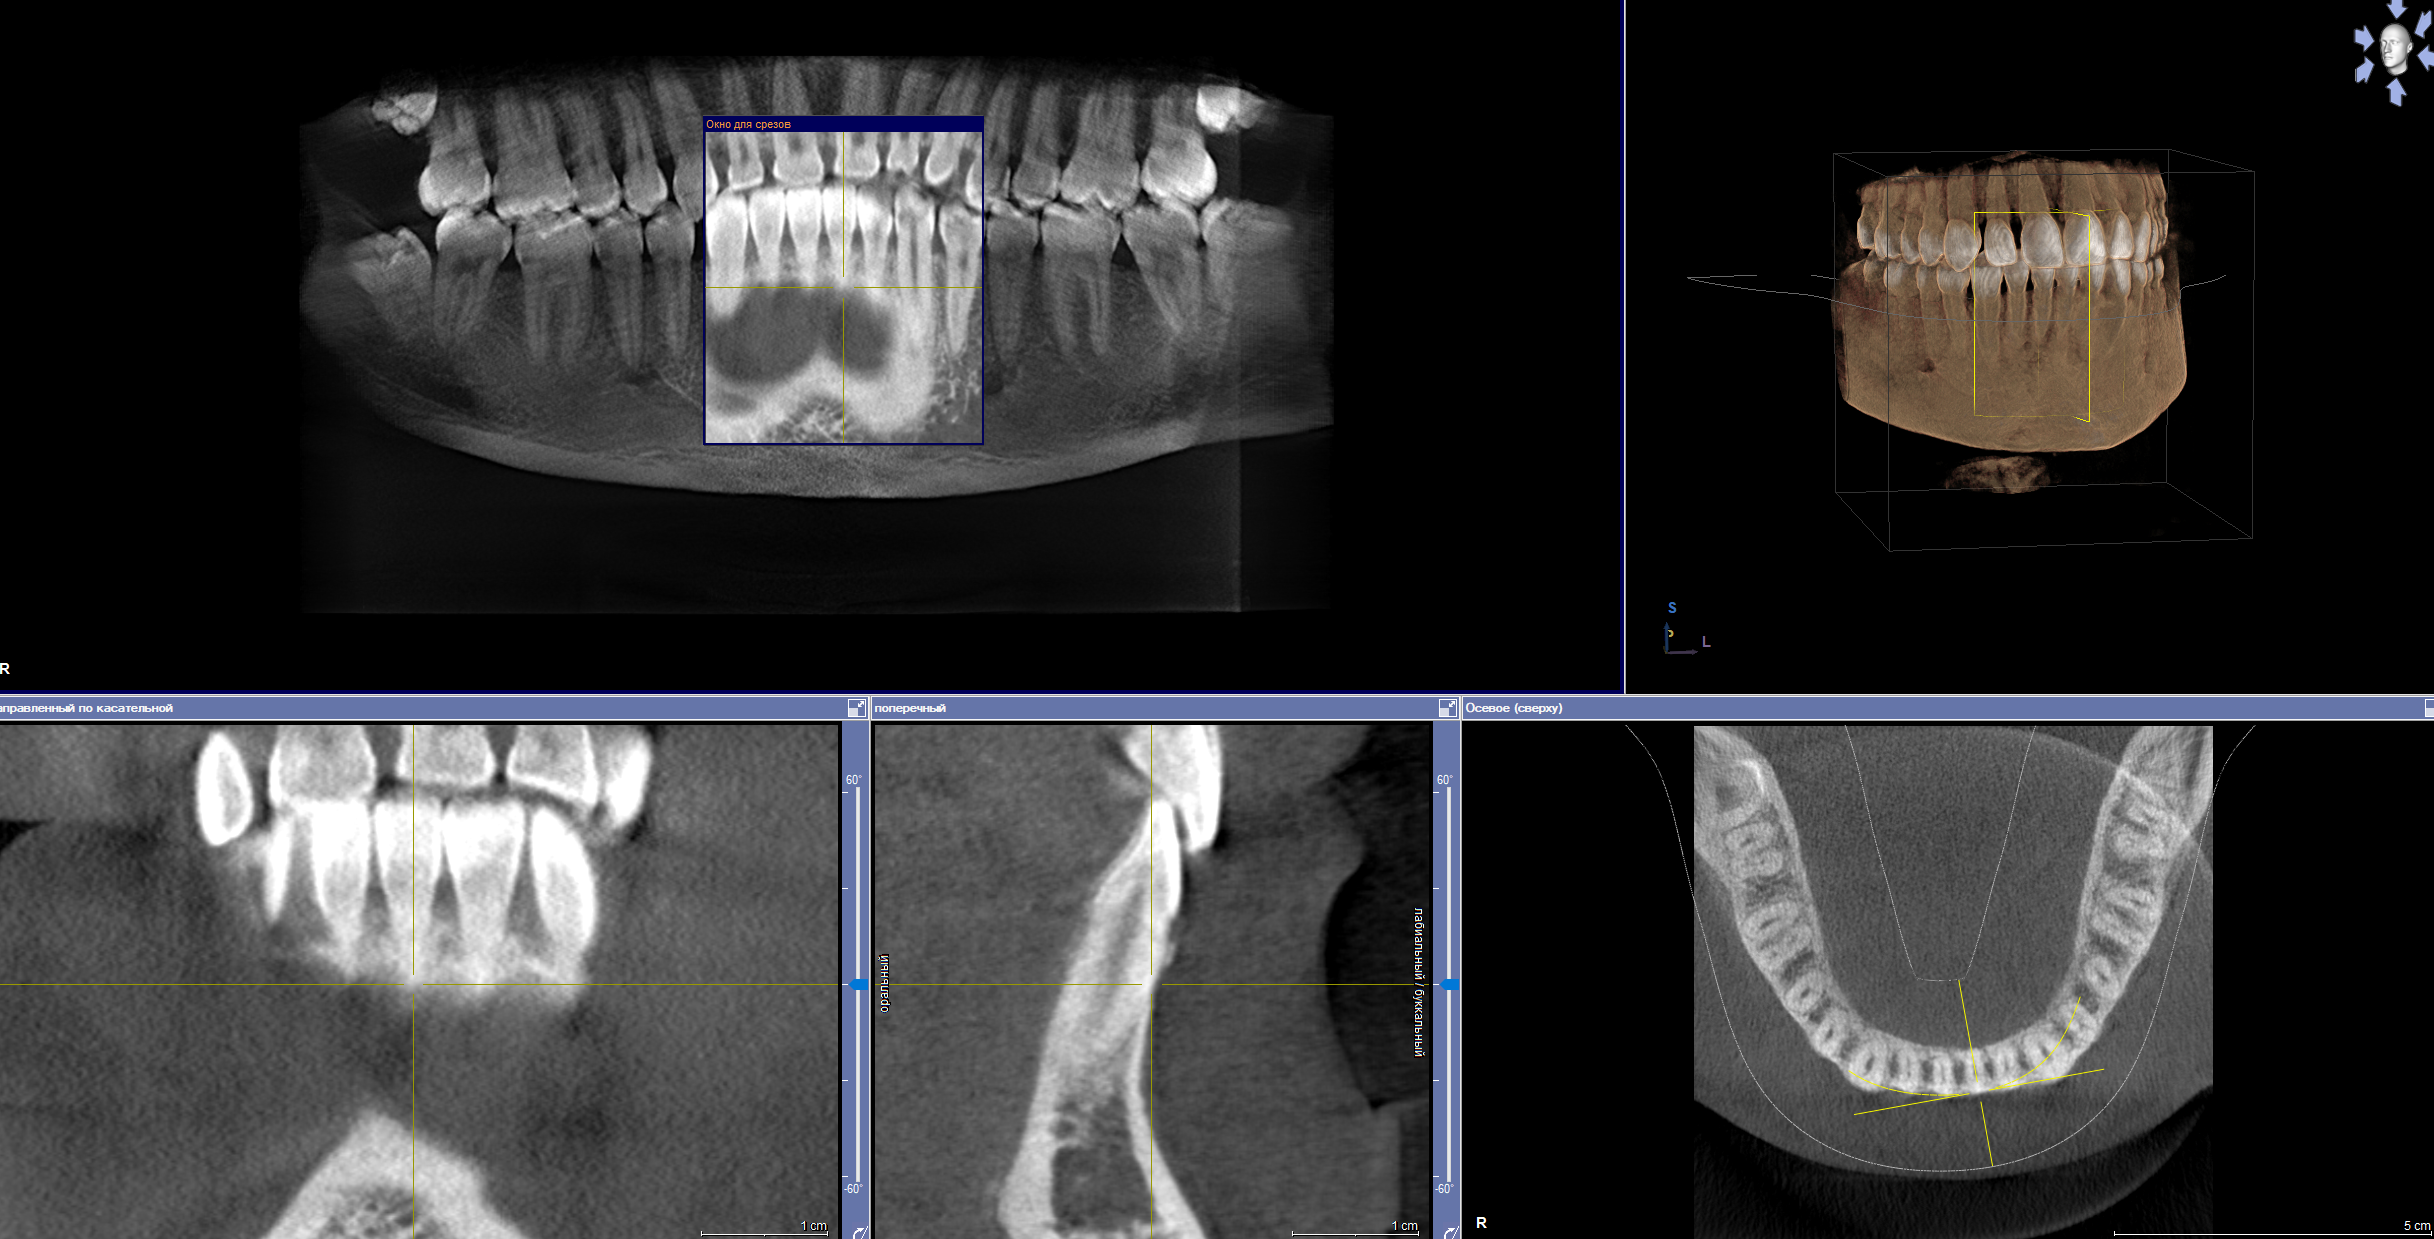

Аноны, добрый вечер.

Посоветуйте пасту зубную после пломбирования и чистки от камня передних зубов.